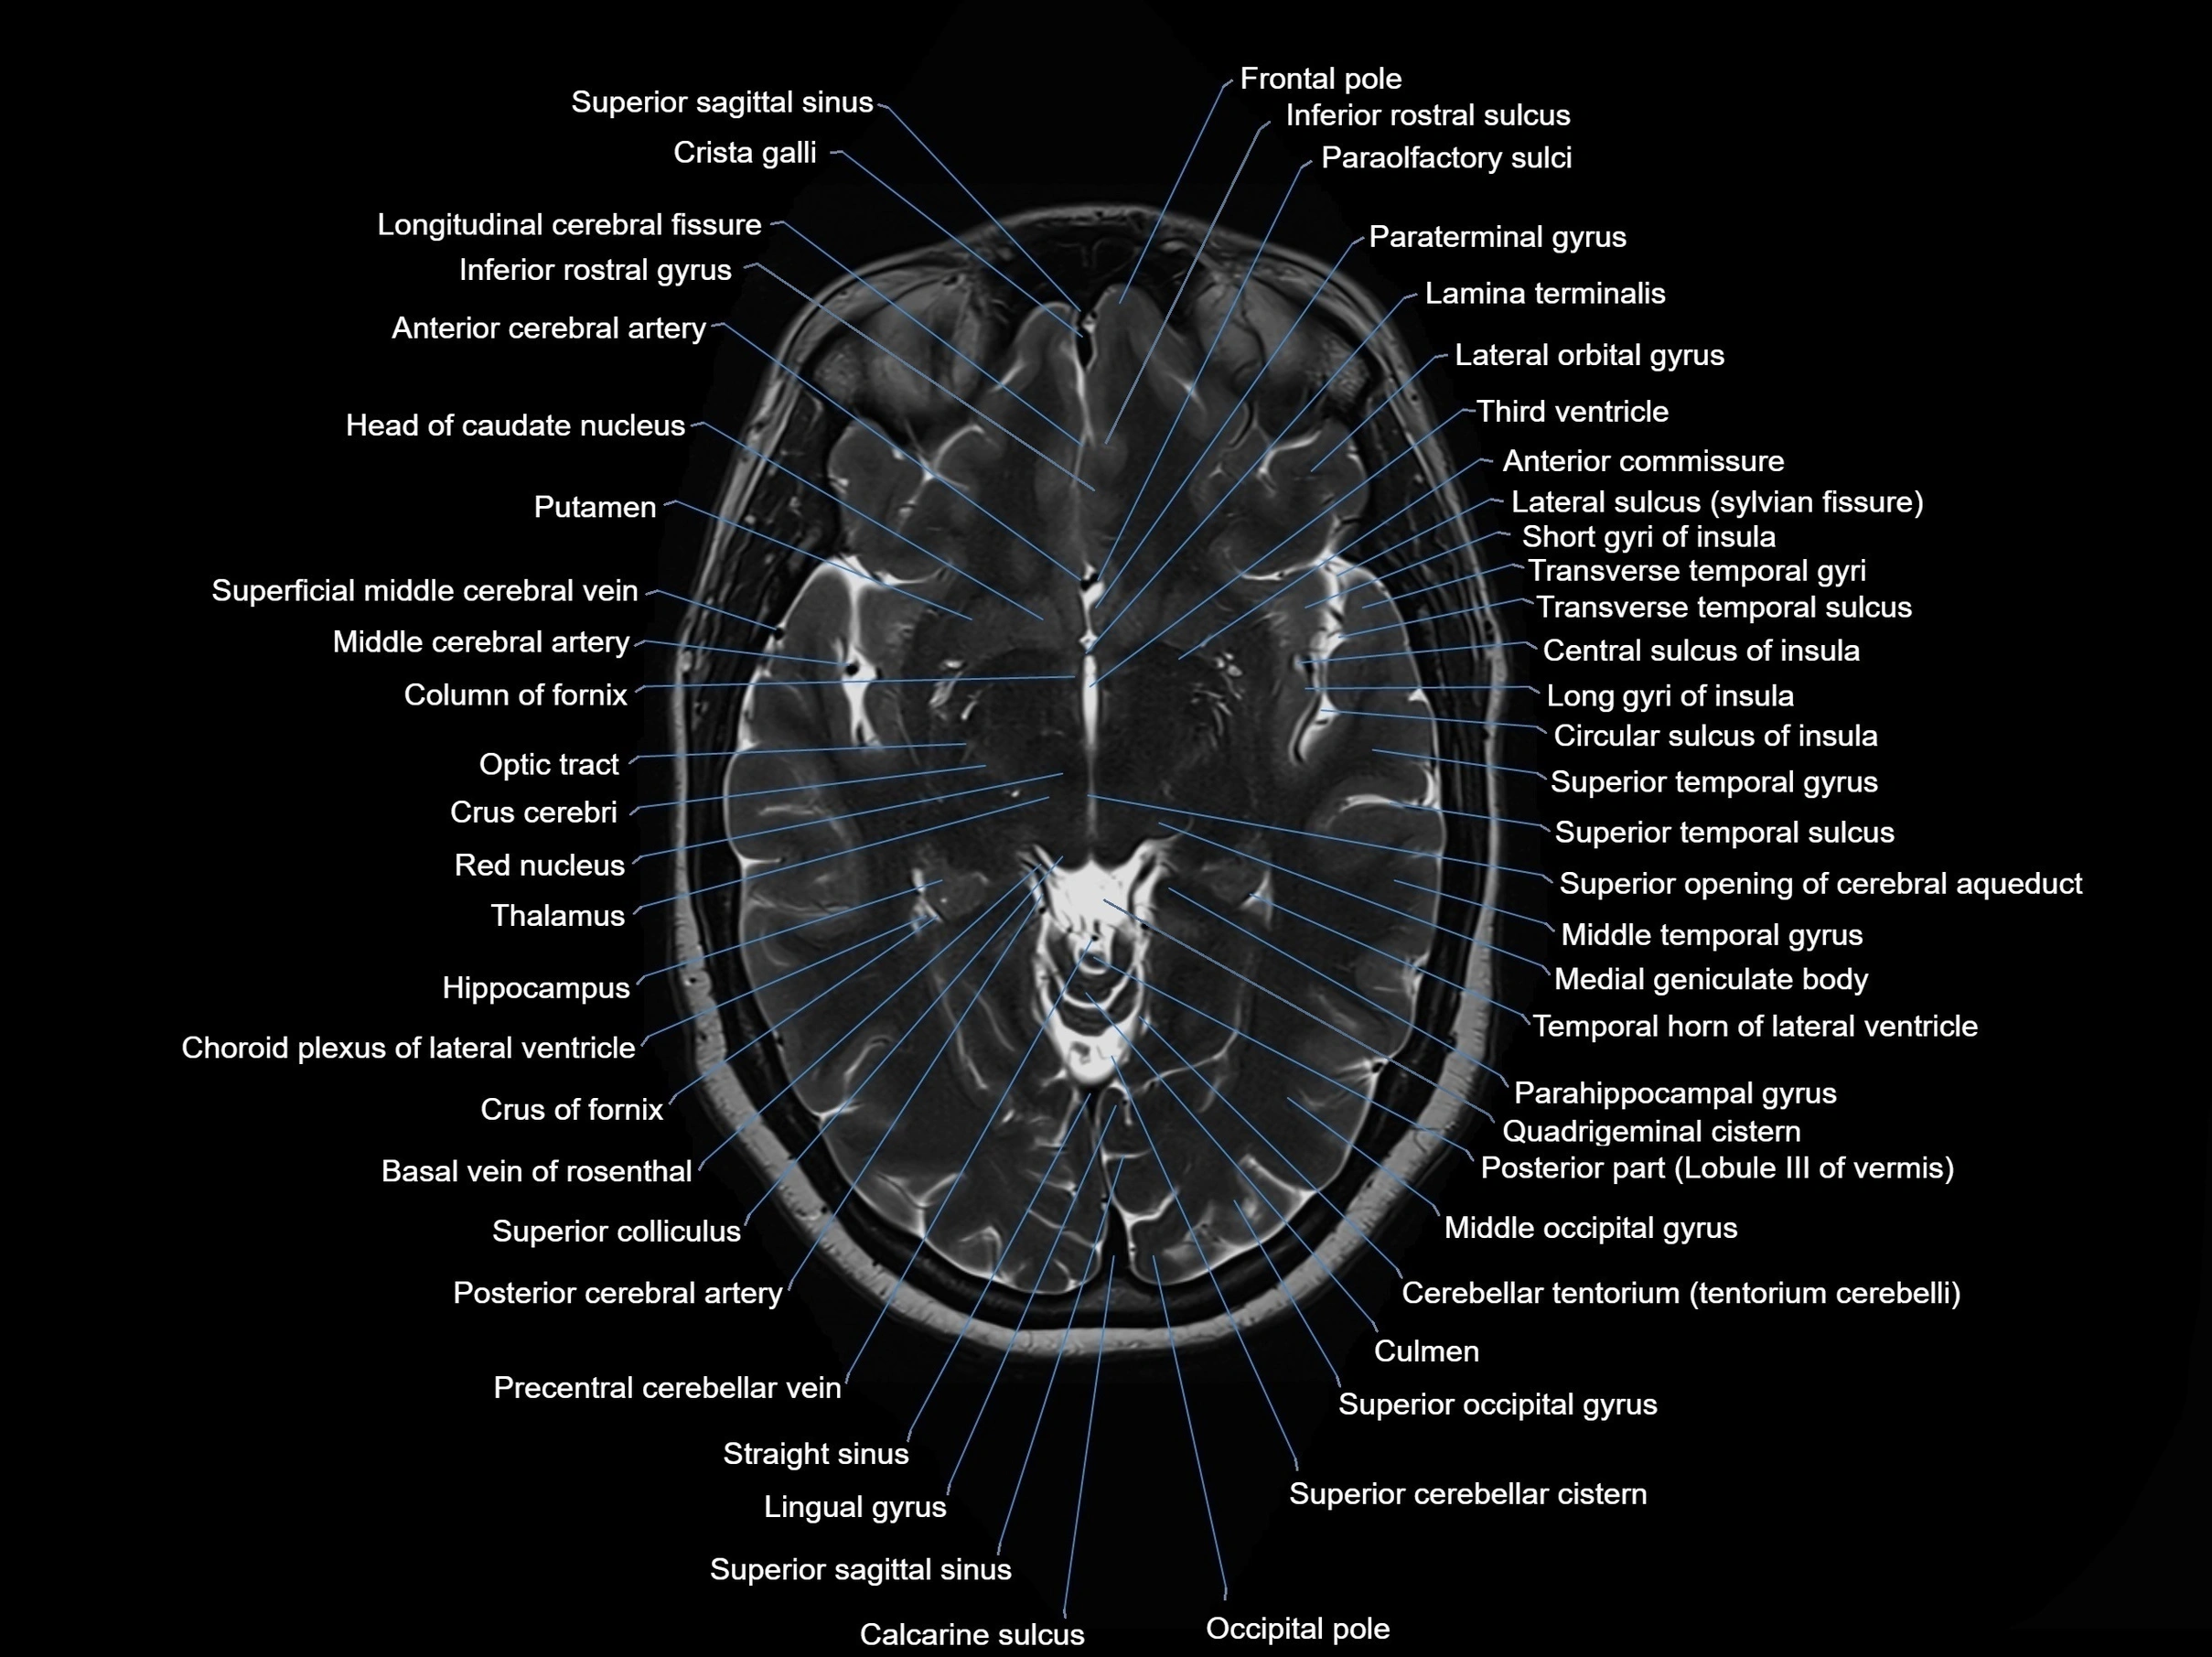

MRI images